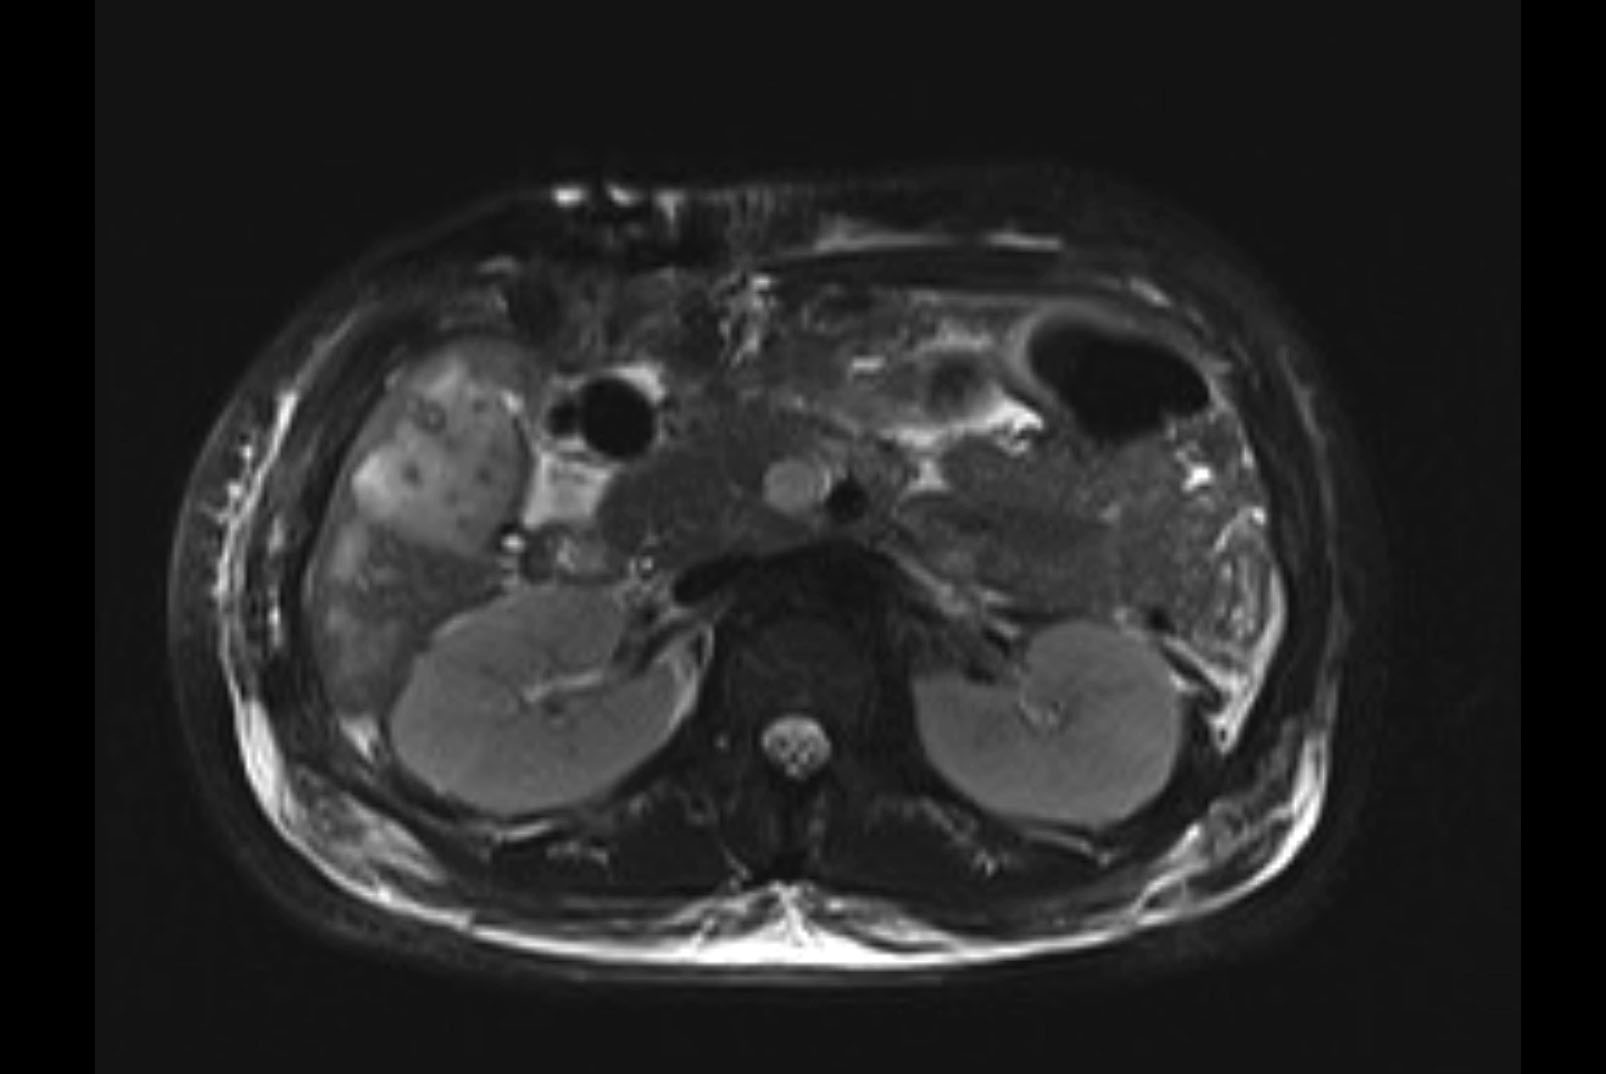

MRI T1

MRI T2